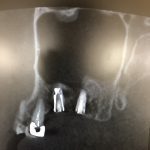

当院では数年前より全てのインプラント治療にコンピューターガイドシステムを取り入れています。

以前も書きましたが手術の計画をPC上で行い、手術道具をオーダーメードで製作し、術前の計画から1mmのズレもなく入れる、という方法を採用しております。ガイドオペとも言います。

利点は、一段と安全で確実な手術ができること、術前にPC上で手術をするので本番がまるで2度めの手術のように行えるため、とてもスムーズに進みます。

高松市でインプラント治療を行っている歯医者は多くありますが、すべての症例でガイドオペを行っている医院はほぼいないようです。

先日の手術も、ガイドオペのお陰でストレスなく、スムーズに進みました

手術時間は実質10数分というところでしょうか

患者様もお疲れ様でした

後日の消毒でもはれ、痛みほぼ無いとのことでした。

後は2ヶ月ほど後に型取りすると最終の被せ物が入って、終わり。もう麻酔の必要のある処置がありません。